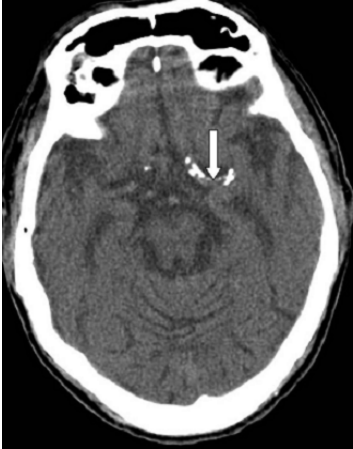

45. 下圖中箭號所指的構造為何?

(A)anterior cerebral artery(ACA) (B)middle cerebral artery(MCA) (C)posterior cerebral artery(PCA) (D)vertebral artery(VA)